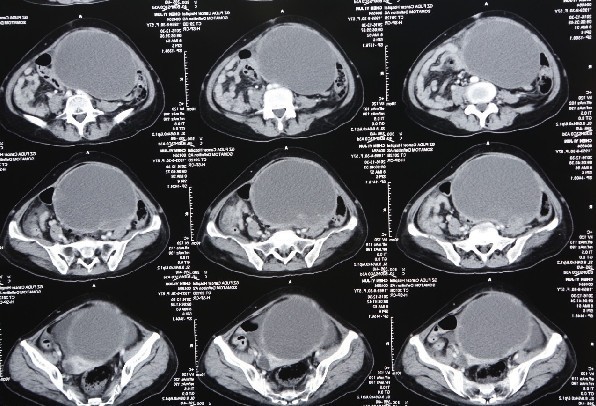

病人术前的CT片